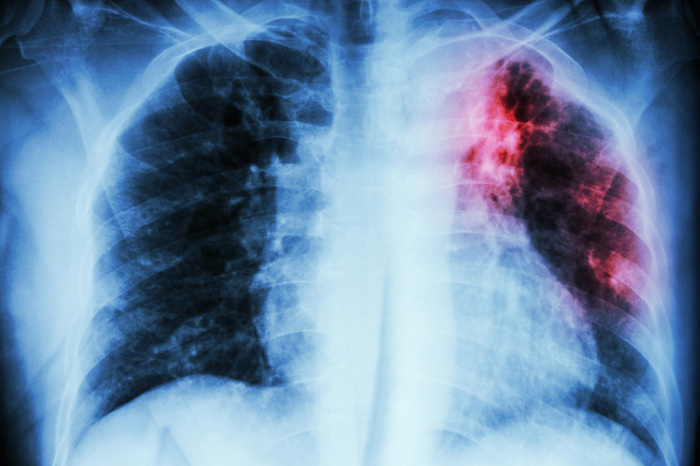

Болезнь романтичных барышень или несколько зарисовок о туберкулёзе

Почему чудесному? Ну как же. Туберкулёз вошёл в моду ещё в 19-м веке, когда бледные, астеничные барышни медленно угасали, пописывая мрачные плохие стихи и посылая таким же бледным юношам засушенные розы. Они ездили лечиться на воды, изящно прикладывали к окровавленным губам батистовые платочки. А потом лежали в гробу все такие красивые. Очень романтично. Ещё туберкулёз подстёгивал половое влечение, что для викторианского общества вообще порнография. Насчёт полового влечения – не знаю, не проверял.

Вернёмся в современность. Заранее ожидаю шквала вопросов – можно ли заразиться туберкулёзом в общественном транспорте? Не буду пугать, но с вами этот процесс, скорее всего, уже произошёл. И неоднократно. Палочка Коха, попадает в организм, где ваш иммунитет набрасывается на неё, агрессивные лейкоциты нападают на болезнетворного чужака, закрывают его своими телами, вокруг палочки образуется известковая или соединительнотканная оболочка, в которой палочка грустит, тоскует и хиреет. Совсем как барышни 19-го века.

Но вы же полноценно питаетесь, не курите, принимаете витамины, в детстве вам сделали прививку от туберкулёза, ведь так? Тогда туберкулёза можно почти не бояться. Если же в одной с вами квартире живёт родственник, покашливающий в платочек, то бегите. Тут уже никакого иммунитета не напасёшься.